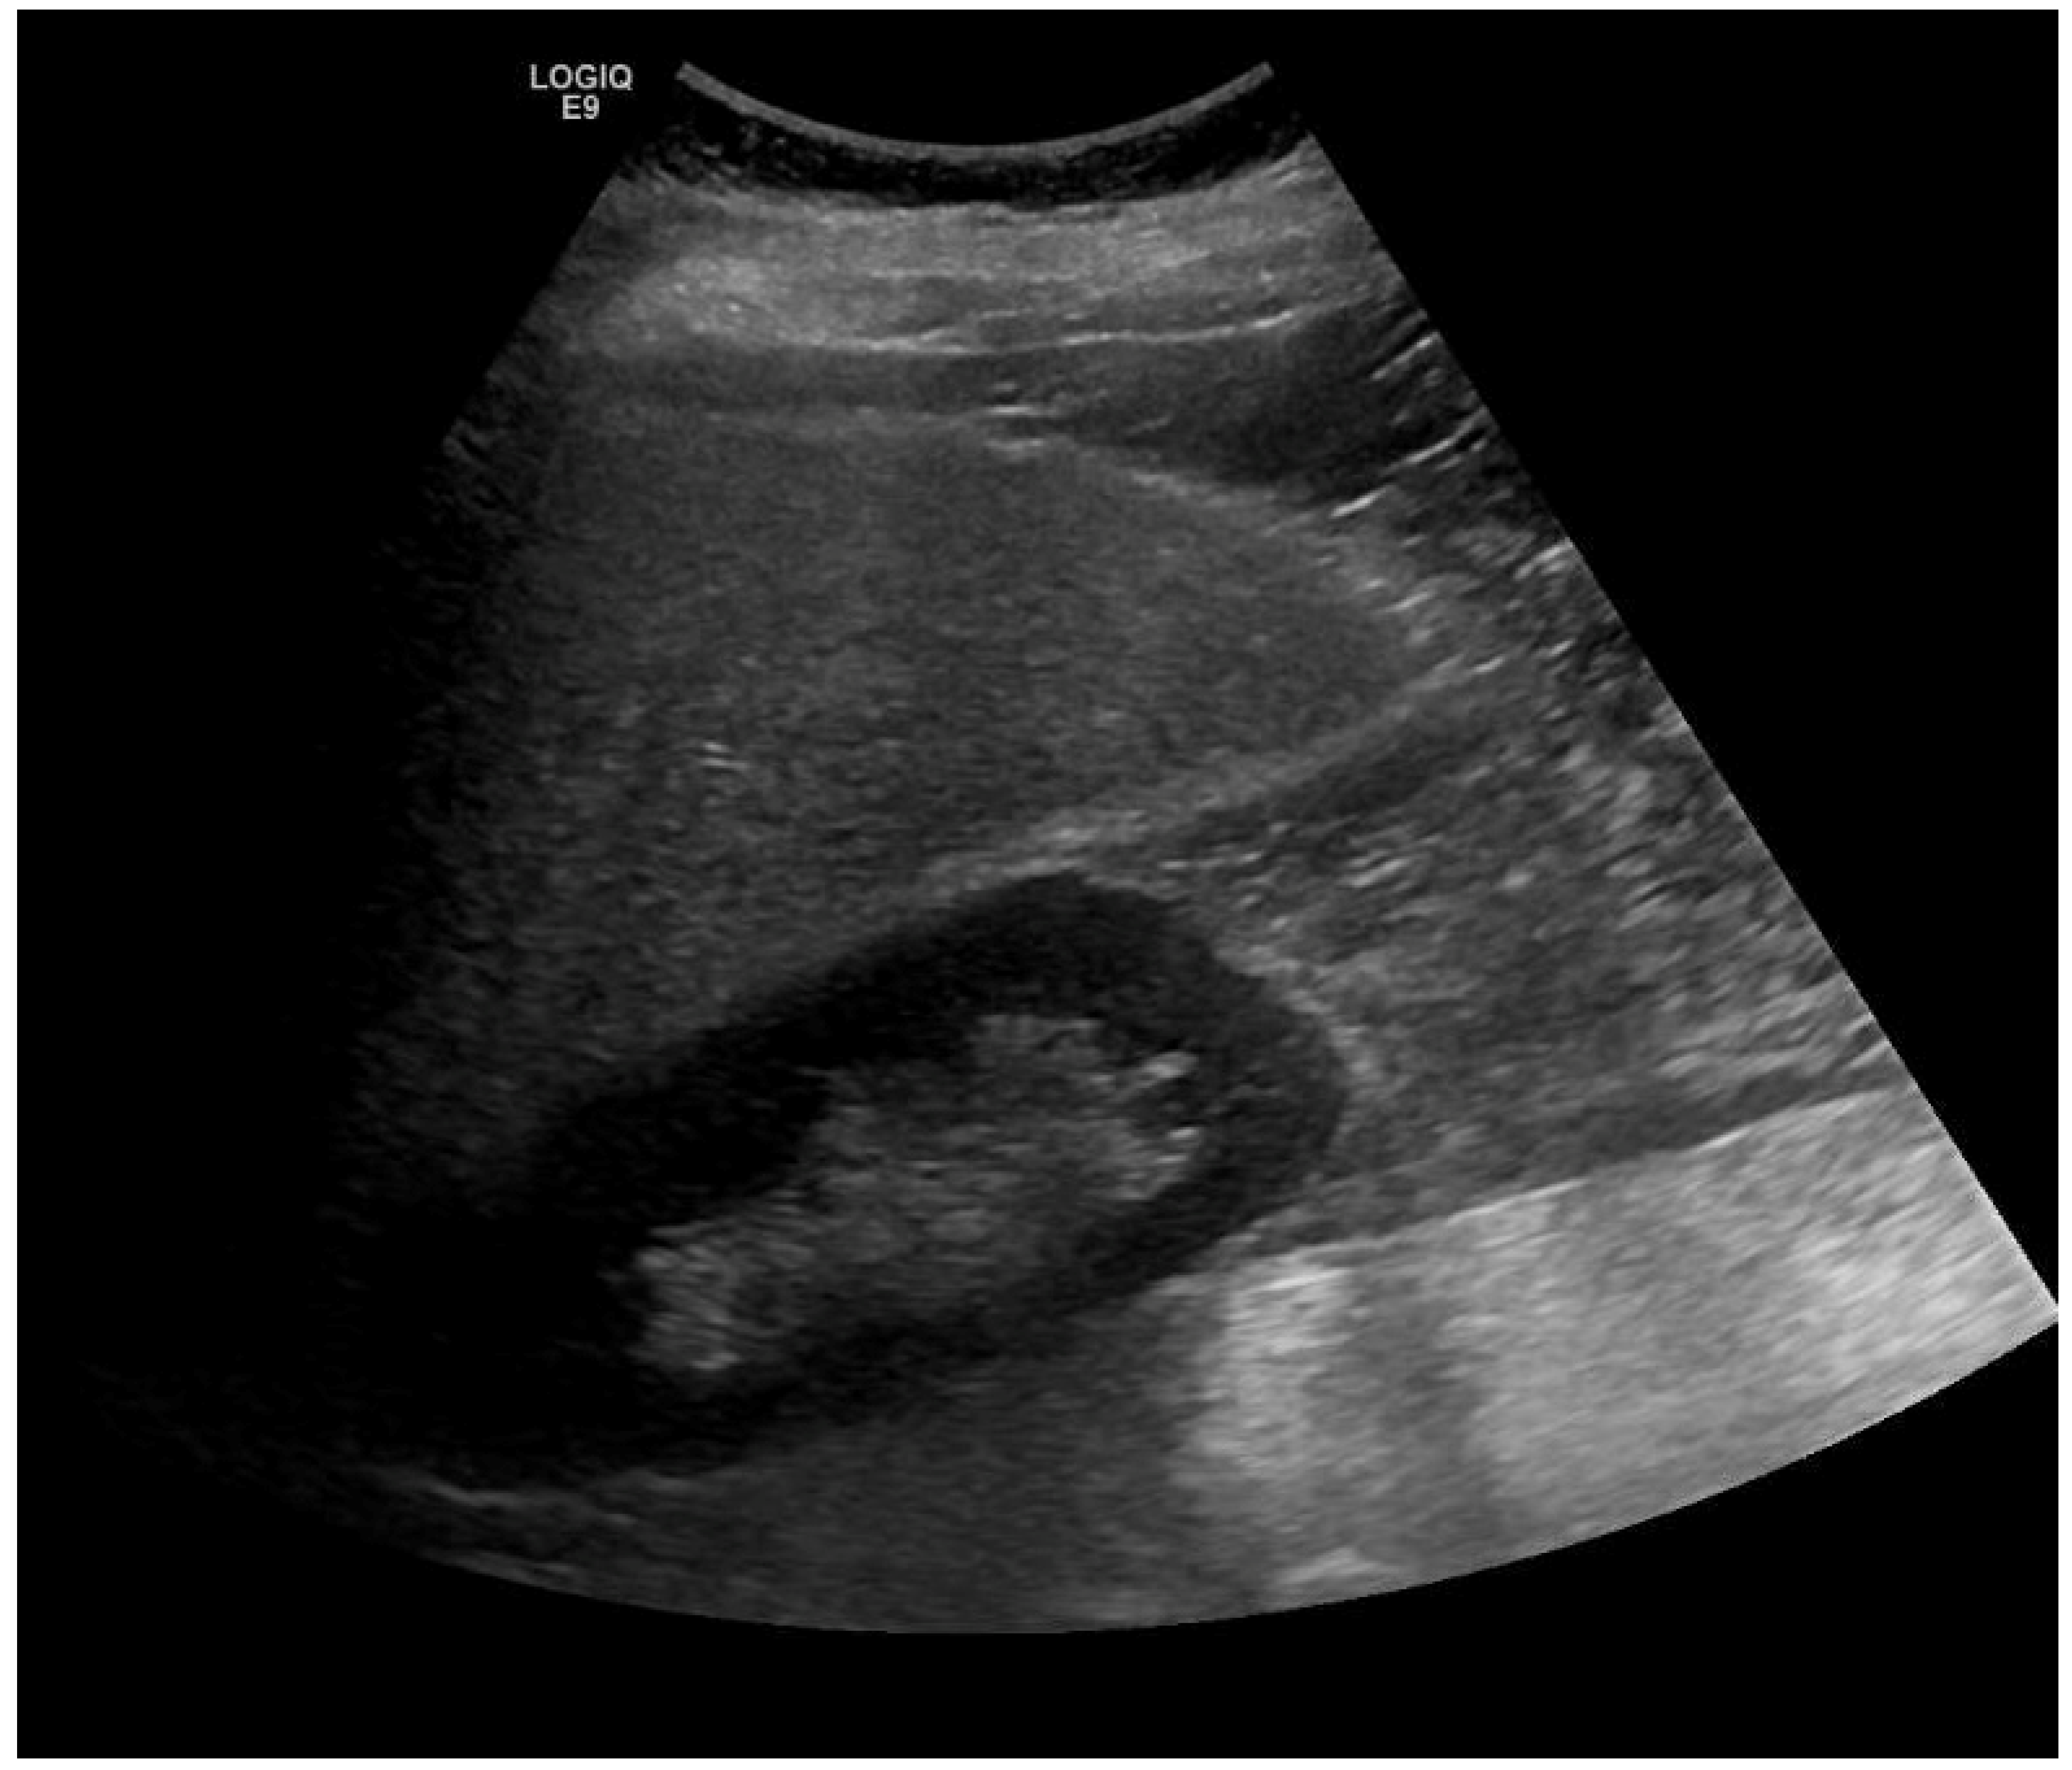

2. Case Report